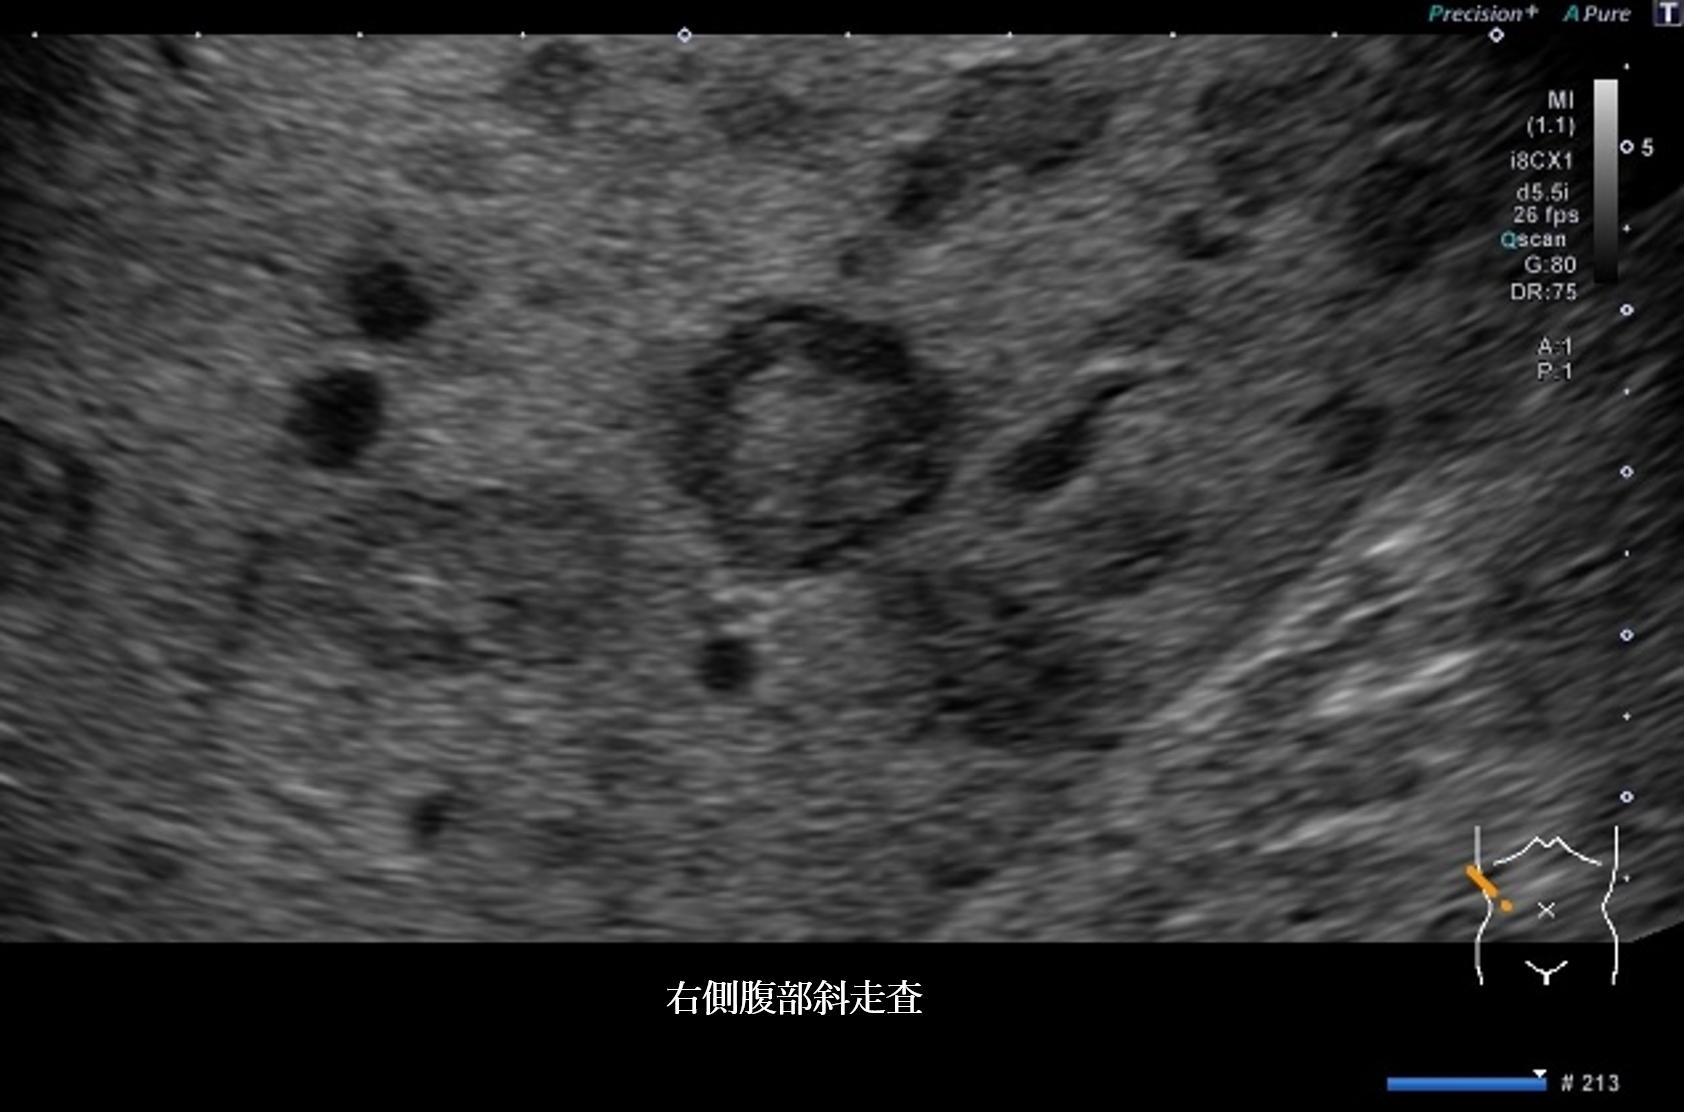

腹部超音波1 動画 右側腹部斜走査(No16-17_A)

腹部超音波1 動画(No16-17_A)

超音波所見より正しいのはどれか

① 肝全体に内部無エコーな腫瘤性病変を多数認める

② 肝全体に腫瘤性病変が多数みられ、辺縁低エコー帯を認める

③ 肝実質は粗雑不均質に観察され、明らかな腫瘤性病変は指摘できない

④ 肝全体に腫瘤性病変が多数みられ、腫瘤内部はモザイクパターンを呈する

⑤ 肝全体に腫瘤性病変が多数みられ、腫瘤辺縁にリング状高エコー像を認める

④ bull’s eye pattern ― 転移性肝腫瘍